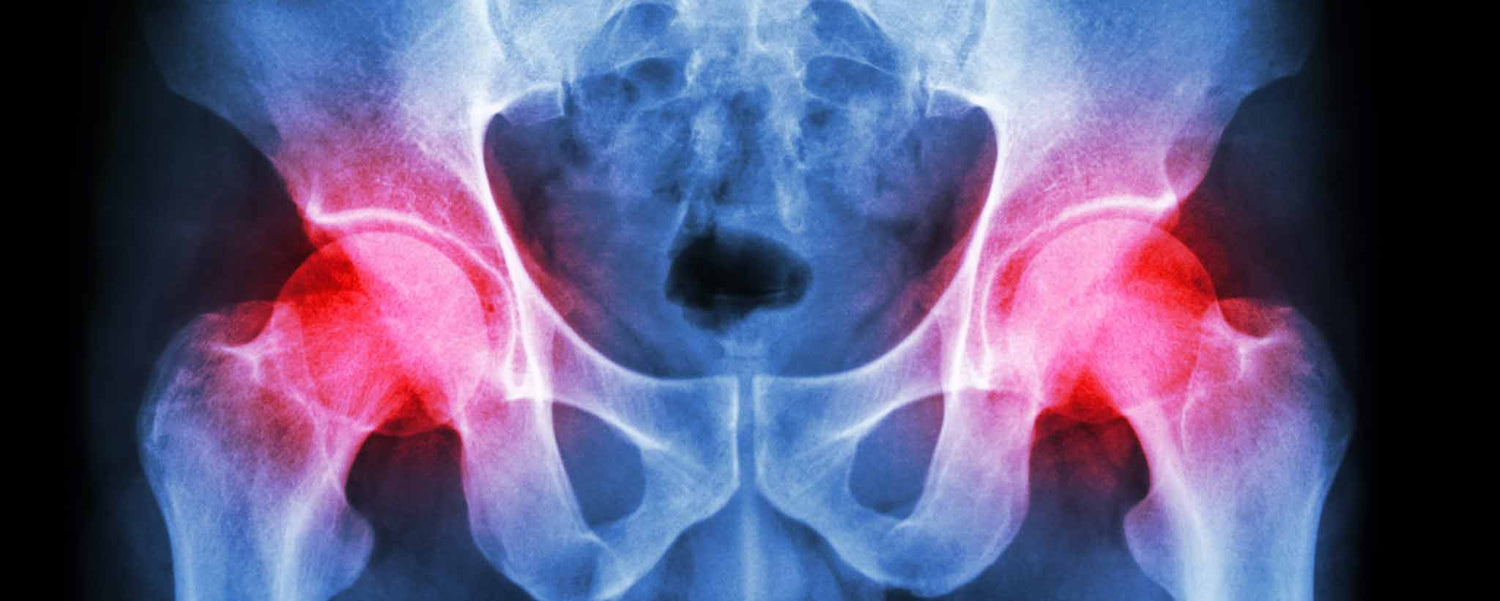

If hip pain interferes with sitting, standing, walking, driving, working, or shopping, you may be a candidate for hip replacement.

Does hip aching interfere with your daily activities like walking or driving? Between the years 2000 and 2010, hip joint replacement surgery increased 200% within the 45–54 age group. Many patients can return to sports and most activities after a successful hip replacement.

- Severe Arthritis – Arthritis is one of the leading causes of progressive hip joint damage. Severe arthritis like osteoarthritis or ankylosing spondylitis may already be causing severe damage to your hip joint. At this point, surgery is a viable option.